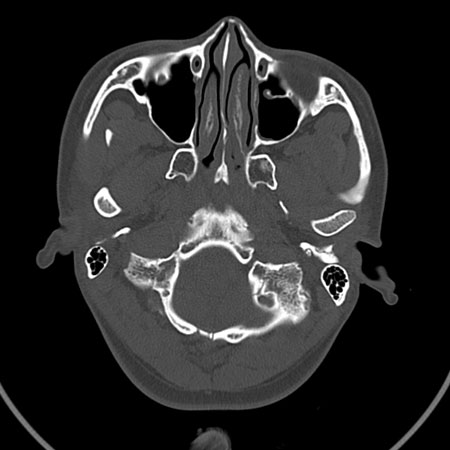

请问各位战友:图示箭头处是否为颅骨骨折?

病史:患者,女,20岁.头部及腹部外伤20分钟.伤后昏迷,无呕吐.头及右侧腰背部疼痛,双侧瞳孔等大,

右肾区叩痛.其它无异常.患者家属否认原有外伤史.

请大家看看是否为颅骨骨折.还是正常变异,或为陈旧骨折.谢谢.

图片未上传完,所见图象示枕骨线样低密度影,边缘锐利,结合外伤史,伤后昏迷,骨折不能除外。

枕骨的线样低密度影锐利、清晰,但正好位于矢状缝的位置,局部无明显软组织肿块,相临及对冲部位脑实质亦无出血及挫裂伤表现。

单就这几层暂不考虑骨折,建议上传完整图片。

楼主所关心的另一个线样影应该是头颅矢状面略偏左,射线正好穿过所致,不需要考虑骨折。

枕骨是单块的,矢状缝是在顶骨而不是在枕骨,枕骨后缘见线状低密度,边缘税利,考虑在骨折存在。

枕后部及左侧颞枕部边缘锐利的线样低密度影,局部软组织无异常,左侧乳突蜂房密度均匀,硬膜下及脑实质内未见出血灶,考虑为正常变异。

枕部考虑骨折。一般的颅逢不会跨越板障,楼主所示枕骨断面两侧板障也不连续。